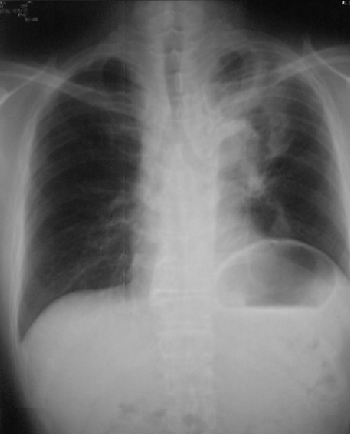

Crp(血液検査)で炎症を察知できるそうですが、ス. Crp(血液検査)で炎症を察知できるそうですが、スキルスや食道癌等の特殊な腫瘍などでも数値は上がるものでしょうか?. 胃がん 検査・診断:[国立がん研究センター がん情報. 胃がんが疑われると、まず血液検査や胃X線検査、内視鏡検査などを行い、病変の有無や場所を調べます(図2)。. 胃胃日旅立ち (胃がん闘病記入院three) ginzadonet. 2002年に胃がん 術後21日 02年2月27日 crp 値17. がんとcrpの関係で質問します。 体のどこかにがんがある場合、血液. がんとCrpの関係で質問します。 体のどこかにがんがある場合、血液検査のcrpやwbcはかなり上がりますか?. Stay a touch !スキルス胃がん Ilife06.Hamazo.Tv. スキルス胃がん患者です。未分化型、ステージIv。腹膜播種、虫垂と横行結腸へ直接浸潤、大腸の2カ所が狭窄、先日肝臓. がんと炎症(crp値) 膵臓がんサバイバーへの挑戦. がん患者が血液検査をすると、Crpが高くなることがあります。 「c反応性蛋白(crp)」は、細胞組織に傷がついたり、臓器や.